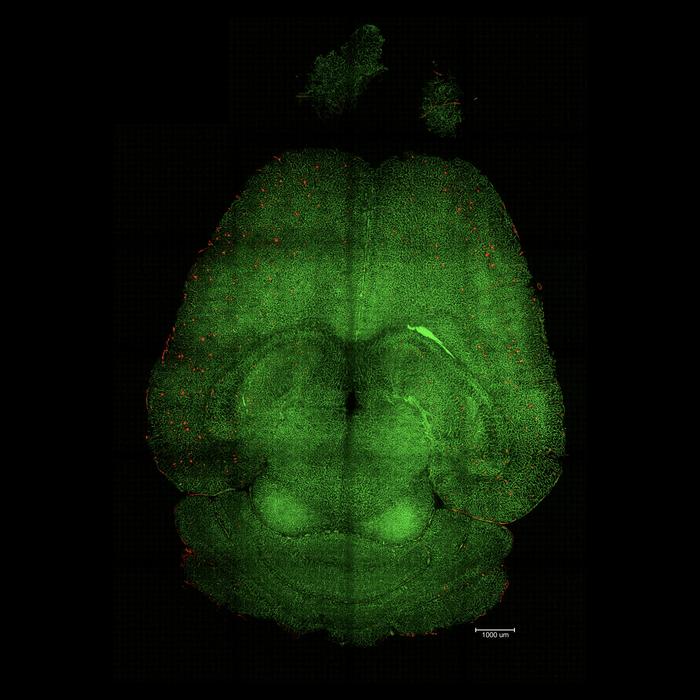

- ENG: Light sheet fluorescence microscope image of mouse brain 12h after being treated with nanoparticles. The brains were analyzed to see the amount of Aβ plaques accumulation. Red: Aβ plaques. Green: vessels from the blood brain barrier.